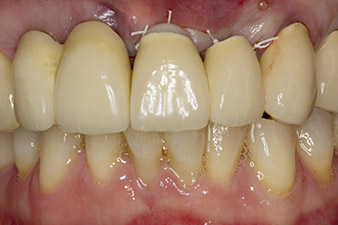

When the patient first presented, teeth 21, 22 and 23 had been restored with splinted crowns, now 19 years old, which were bonded to the implants at positions 12/11 by an attachment (cf. Fig. 2).

Following primary healing, the soft tissues were shaped using the basally lined bridge. Two months later the site was exposed by a slightly palatal alveolar ridge incision (Fig 2). The dimensions of the alveolar bone proved to be sufficient at position 22. Figures 2 and 4 show the preparation of the implant bed, the tapping and the implantation using Implantmed.